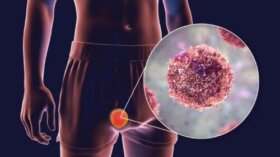

기형종은 다능성 줄기세포에서 발생하는 종양의 일종이다. 그리스어에서 유래한 용어로 ‘teratos’는 ‘괴물,’ 접미사인 ‘-oma’는 ‘종양’을 뜻한다. 즉, 기형종 정의는 ‘괴물 같은 종양’이다. 특이한 외형 때문에 괴물 같은 종양이라 불리는데 종양에 머리카락, 치아, 근육, 뼈 등이 함께 자랄 수 있다. 기형종을 생성하는…